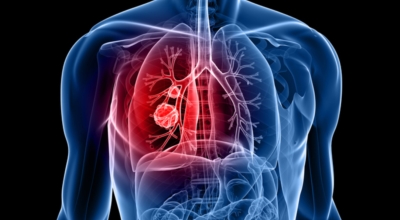

인체가 순조롭게 기능을 발휘하려면 폐 건강이 필수다. 폐는 인체가 효율적으로 움직이는 데 있어 바퀴 안에 있는 톱니 같은 역할을 하기 때문이예요. 산소를 제공하는 폐 기능이 감소하게되면 폐렴이나, 만성 폐쇄성 폐질환(COPD), 천식 등 정도가 심한 호흡기 질환 발생 위험이 증가해요. 이런 질병들은 폐를 공격해 숨쉬기 힘들게 만들어요.

특별히 현대 사회에서 폐는 가장 시달리는 장기 중 한 종류다. 가지가지 공해 성분으로 오염된 공기에 미세 먼지, 황사까지 더하면 폐 안쪽에 있는 허파꽈리(폐포)부터 정도가 심한 훼손을 입습니다. 따라서 폐 건강을 증진시키기 위하여는 폐에 좋은 음식을 섭취할 필요가 있어요.